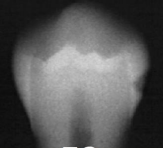

classify this according to radiographic presentation of the ADA

E2

classify this lesion according to the ADA and ICDAS/ICCMS systems

caries within the inner half of the enamel: RA1, E1